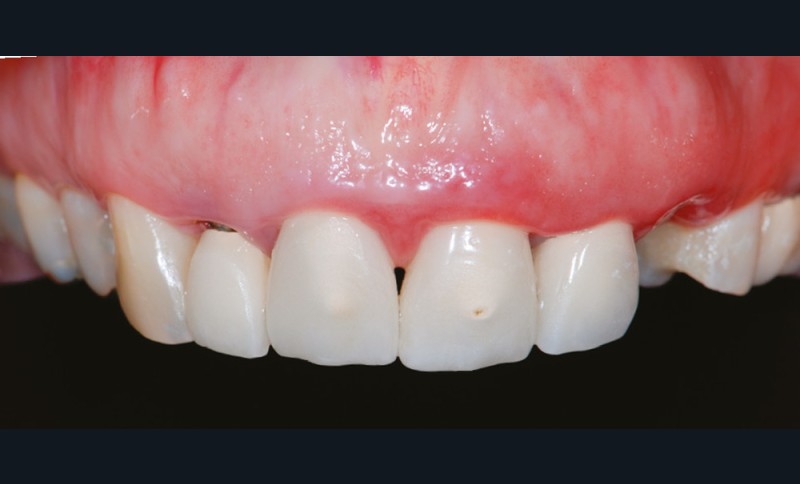

1 – Le système d’attache d’une dent est composé de l’os alvéolaire, du ligament alvéolo-dentaire et de l’attache épithélio-conjonctive ou attache supra-crestale. L’attache supra-crestale, anciennement confondue avec l’espace biologique, est un espace d’environ 2 mm [1] occupé par l’attache conjonctive (1 mm) et l’attache épithéliale (1 mm). Il est normalement visible à la radiographie rétro-alvéolaire entre le sommet de la crête osseuse et la jonction émail-cément. Comme une dent possède naturellement un sulcus, certains auteurs estiment qu’il convient d’y ajouter au moins 1 mm de sulcus libre de toute structure prothétique [2]. On peut donc considérer l’espace biologique comme un « espace clinique sanctuarisé » de 3 mm au sommet de la crête osseuse alvéolaire, nécessaire à la santé et à la stabilité parodontale. La violation de l’espace biologique génère un traumatisme parodontal aboutissant à des récessions gingivales ou des gingivites prothétiques (fig. 1a-b).